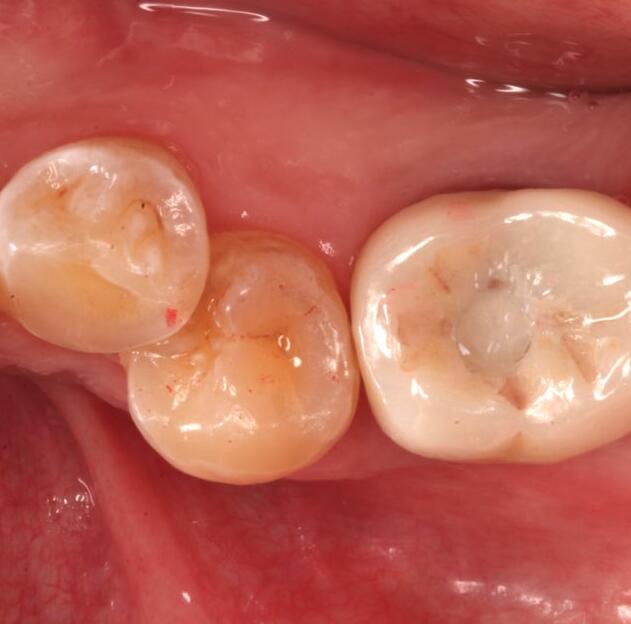

活動(dòng)義齒是一種可自行摘帶的牙齒修復(fù)的方法,選擇活動(dòng)義齒來(lái)恢復(fù)牙齒的使用狀態(tài),是因?yàn)檫@種調(diào)節(jié)方式對(duì)我的口腔損傷比較小。在做完手術(shù)后,不會(huì)感覺(jué)我的牙齒有不舒適的情況,而且平時(shí)自己就有戴假牙的習(xí)慣,所以做活動(dòng)義齒反而會(huì)覺(jué)得更方便,更適應(yīng)一些。在做活動(dòng)義齒的調(diào)節(jié)時(shí),我對(duì)活動(dòng)義齒的材料沒(méi)有過(guò)敏反應(yīng),并且因?yàn)槔钚γ丰t(yī)生的牙齒修復(fù)調(diào)節(jié)的手法嫻熟,我在做了牙齒的調(diào)節(jié)后,沒(méi)有出現(xiàn)其他不良的情況。